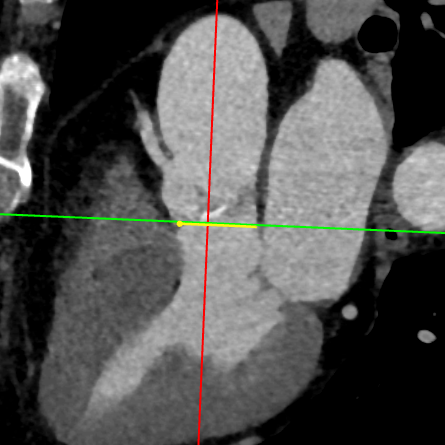

武汉协和董念国团队对该病例进行了缜密探讨,该病例为老年男性,主动脉瓣中重度狭窄,术前左室舒张功能减低。患者病例CT和心超数据显示瓣环周长:90.2mm,瓣下4mm流出道周长:97.5mm,窦部空间相对小,单纯无冠瓣瓣叶钙化,三叶瓣。左冠风险较高,缜密分析瓣叶遮盖率>50%,术中可能存在阻挡风险,需要术中球囊扩张时仔细辨认,并准备冠脉保护策略。综合评估考虑右股动脉更适宜为主入路。经过团队严谨的评估及充分的讨论,决定先行25mm球囊预扩并进一步确认冠脉风险,并准备TAV29和TAV32规格的ProStyle预装式可回收TAVR系统。

LOVT

Annlus

瓣上2mm

瓣上  4mm

瓣上6mm

瓣上8mm

瓣上10mm

瓣上12mm

左冠评估

右冠评估

瓣环切线位窦部空间

左室空间

工作位1(共平面/左冠切)

工作位2(无窦切线/左右重叠)